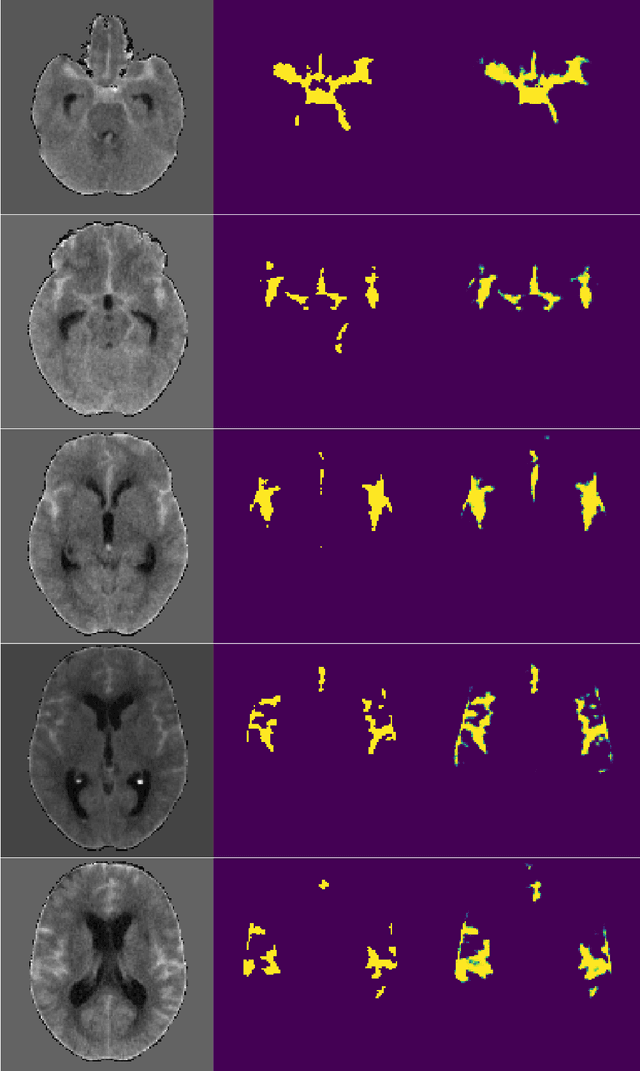

Abstract:Accurately assessing tumor removal is paramount in the management of glioblastoma. We developed a pipeline using MRI scans and neural networks to segment tumor subregions and the surgical cavity in postoperative images. Our model excels in accurately classifying the extent of resection, offering a valuable tool for clinicians in assessing treatment effectiveness.